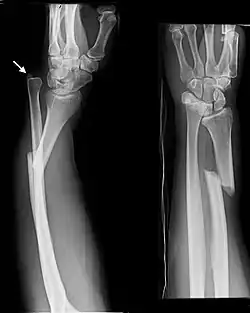

Fractures of the ulna can occur at different levels of the bone: near the wrist, in the middle or near the elbow.[2] The fracture may be confined to the ulna or accompanied with damage to the radius or the wrist or elbow joints.[2]

- Monteggia fracture - a fracture of the near to elbow end of the ulna with the dislocation of the head of the radius at the elbow joint.[2]

Monteggia Fracture (fracture of proximal ulna) -